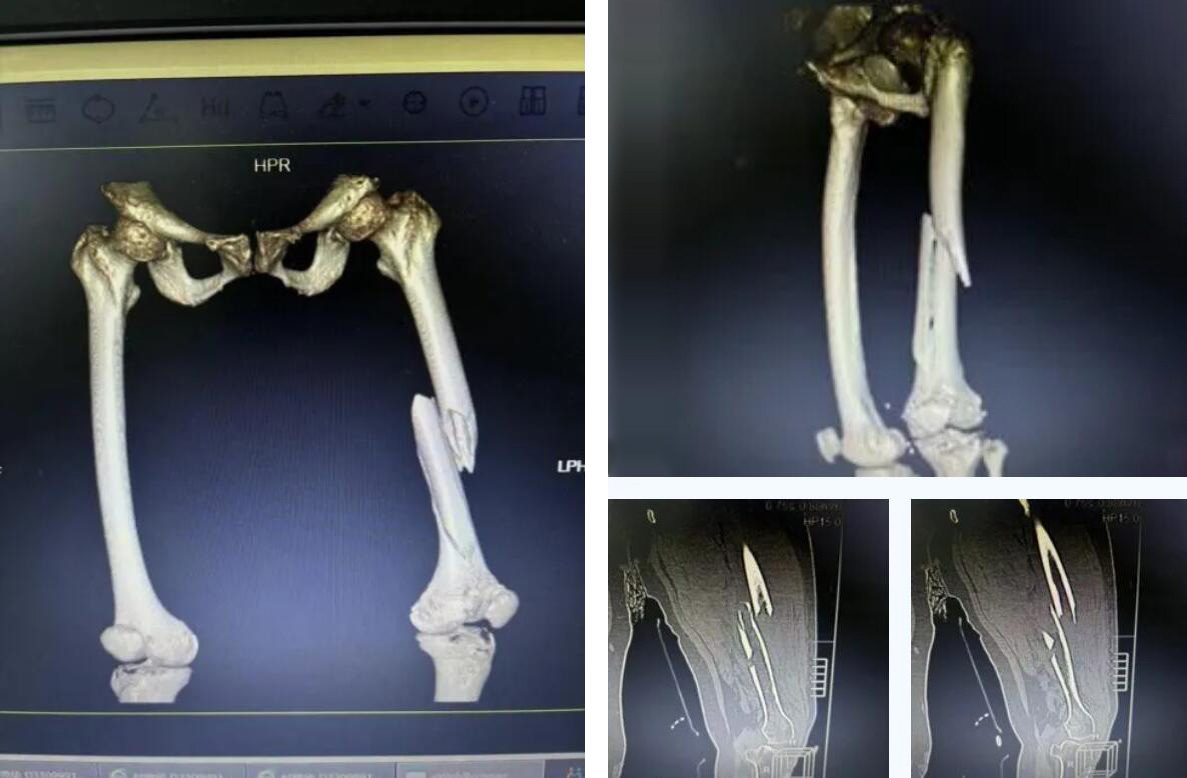

術(shù)前患者骨折CT影像

股骨,即人體的大腿骨,是全身最長(zhǎng)的骨骼,對(duì)于高齡老人,尤其是超過(guò)90歲的超高齡老人而言,髖部骨折常被稱為“人生最后一次骨折”,死亡率極高。

而俞奶奶的股骨中段的多段骨折,手術(shù)難度和風(fēng)險(xiǎn)更是呈幾何級(jí)數(shù)增加,傳統(tǒng)的開(kāi)放手術(shù)創(chuàng)傷大、出血多,老人脆弱的心肺功能難以承受。